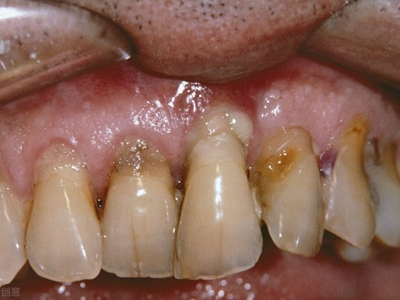

牙龈退缩上牙龈萎缩严重露出深黄色牙根图

牙龈退缩患者的上牙龈退缩比较严重,能够看到原本无法看到的部分牙根,比原来的牙齿变长,牙根位置能够看到很多牙结石,应尽快处理,以免退缩更严重。